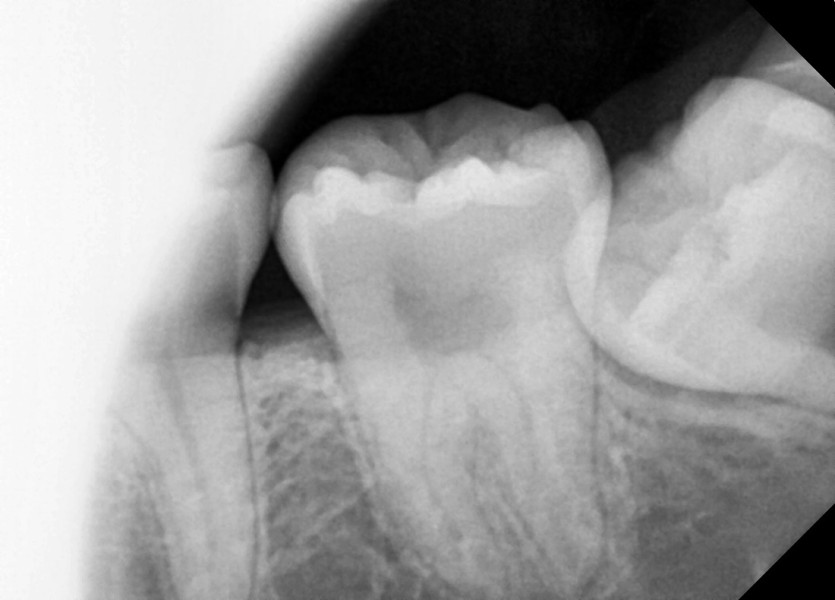

#38,48 사랑니 발치

구강 외과 전문의가 당일 발치했습니다.